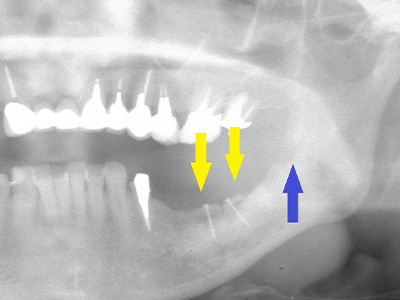

50代女性。左写真黄色矢印部の歯の周囲は、重度歯周病で大きく歯槽骨が吸収されてしまい、下方赤色矢印部の神経まで距離がなく、インプラント埋入には骨の高さが不足しています。

そこで、青色矢印部、智歯周辺の骨を採取し黄色矢印部に骨片を移植、チタン製の小さなスクリューで骨片を固定して、骨の生着を待ちます。